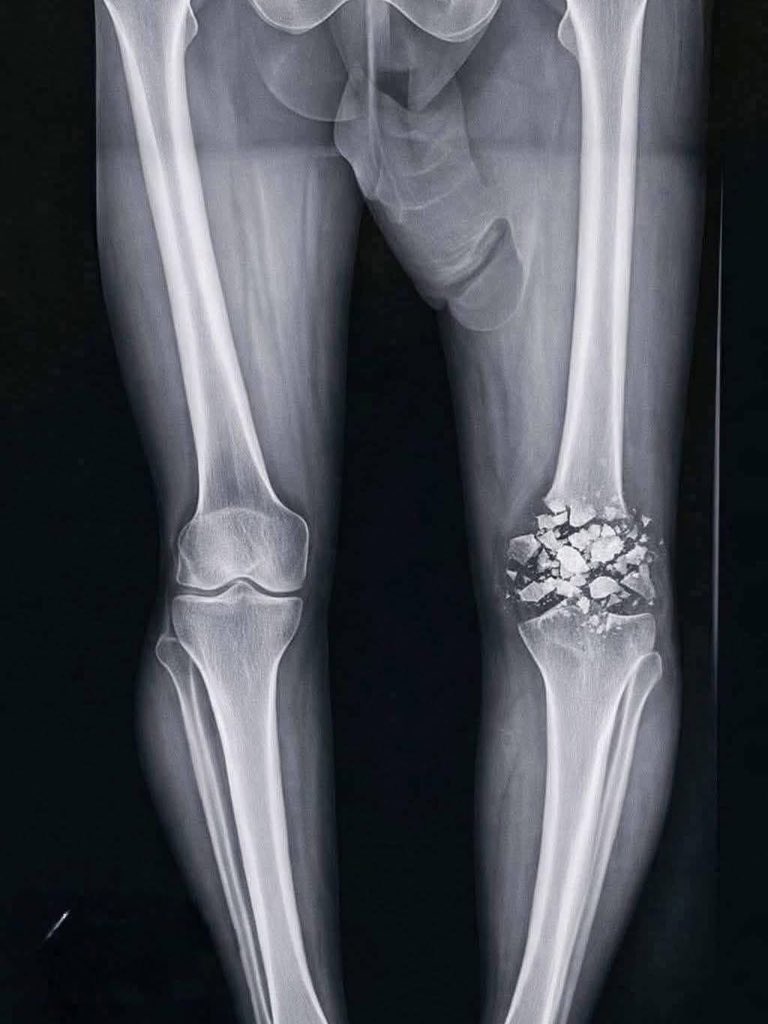

🚨 Breaking: Szymon Marciniak out for 6 months with ACL injury. Devastating blow for Real Madrid – now they have to play Bayern in a fair 11 vs 11? No pre-booked penalties, no red cards, no ignored offsides. Our deep condolences to Florentino and Real Madrid. 💔 #Realmadrid